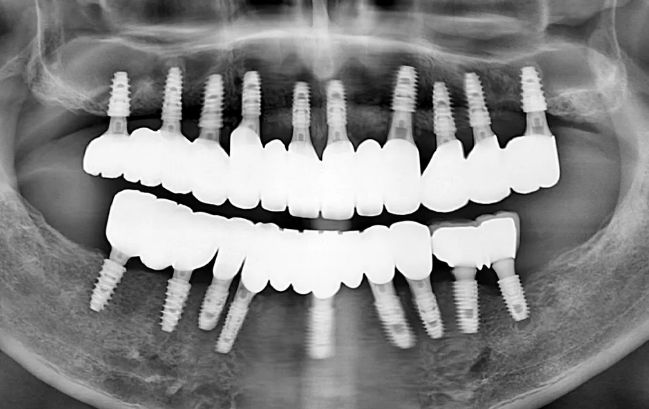

50대 남성, 원데이 전체 임플란트 18개 식립